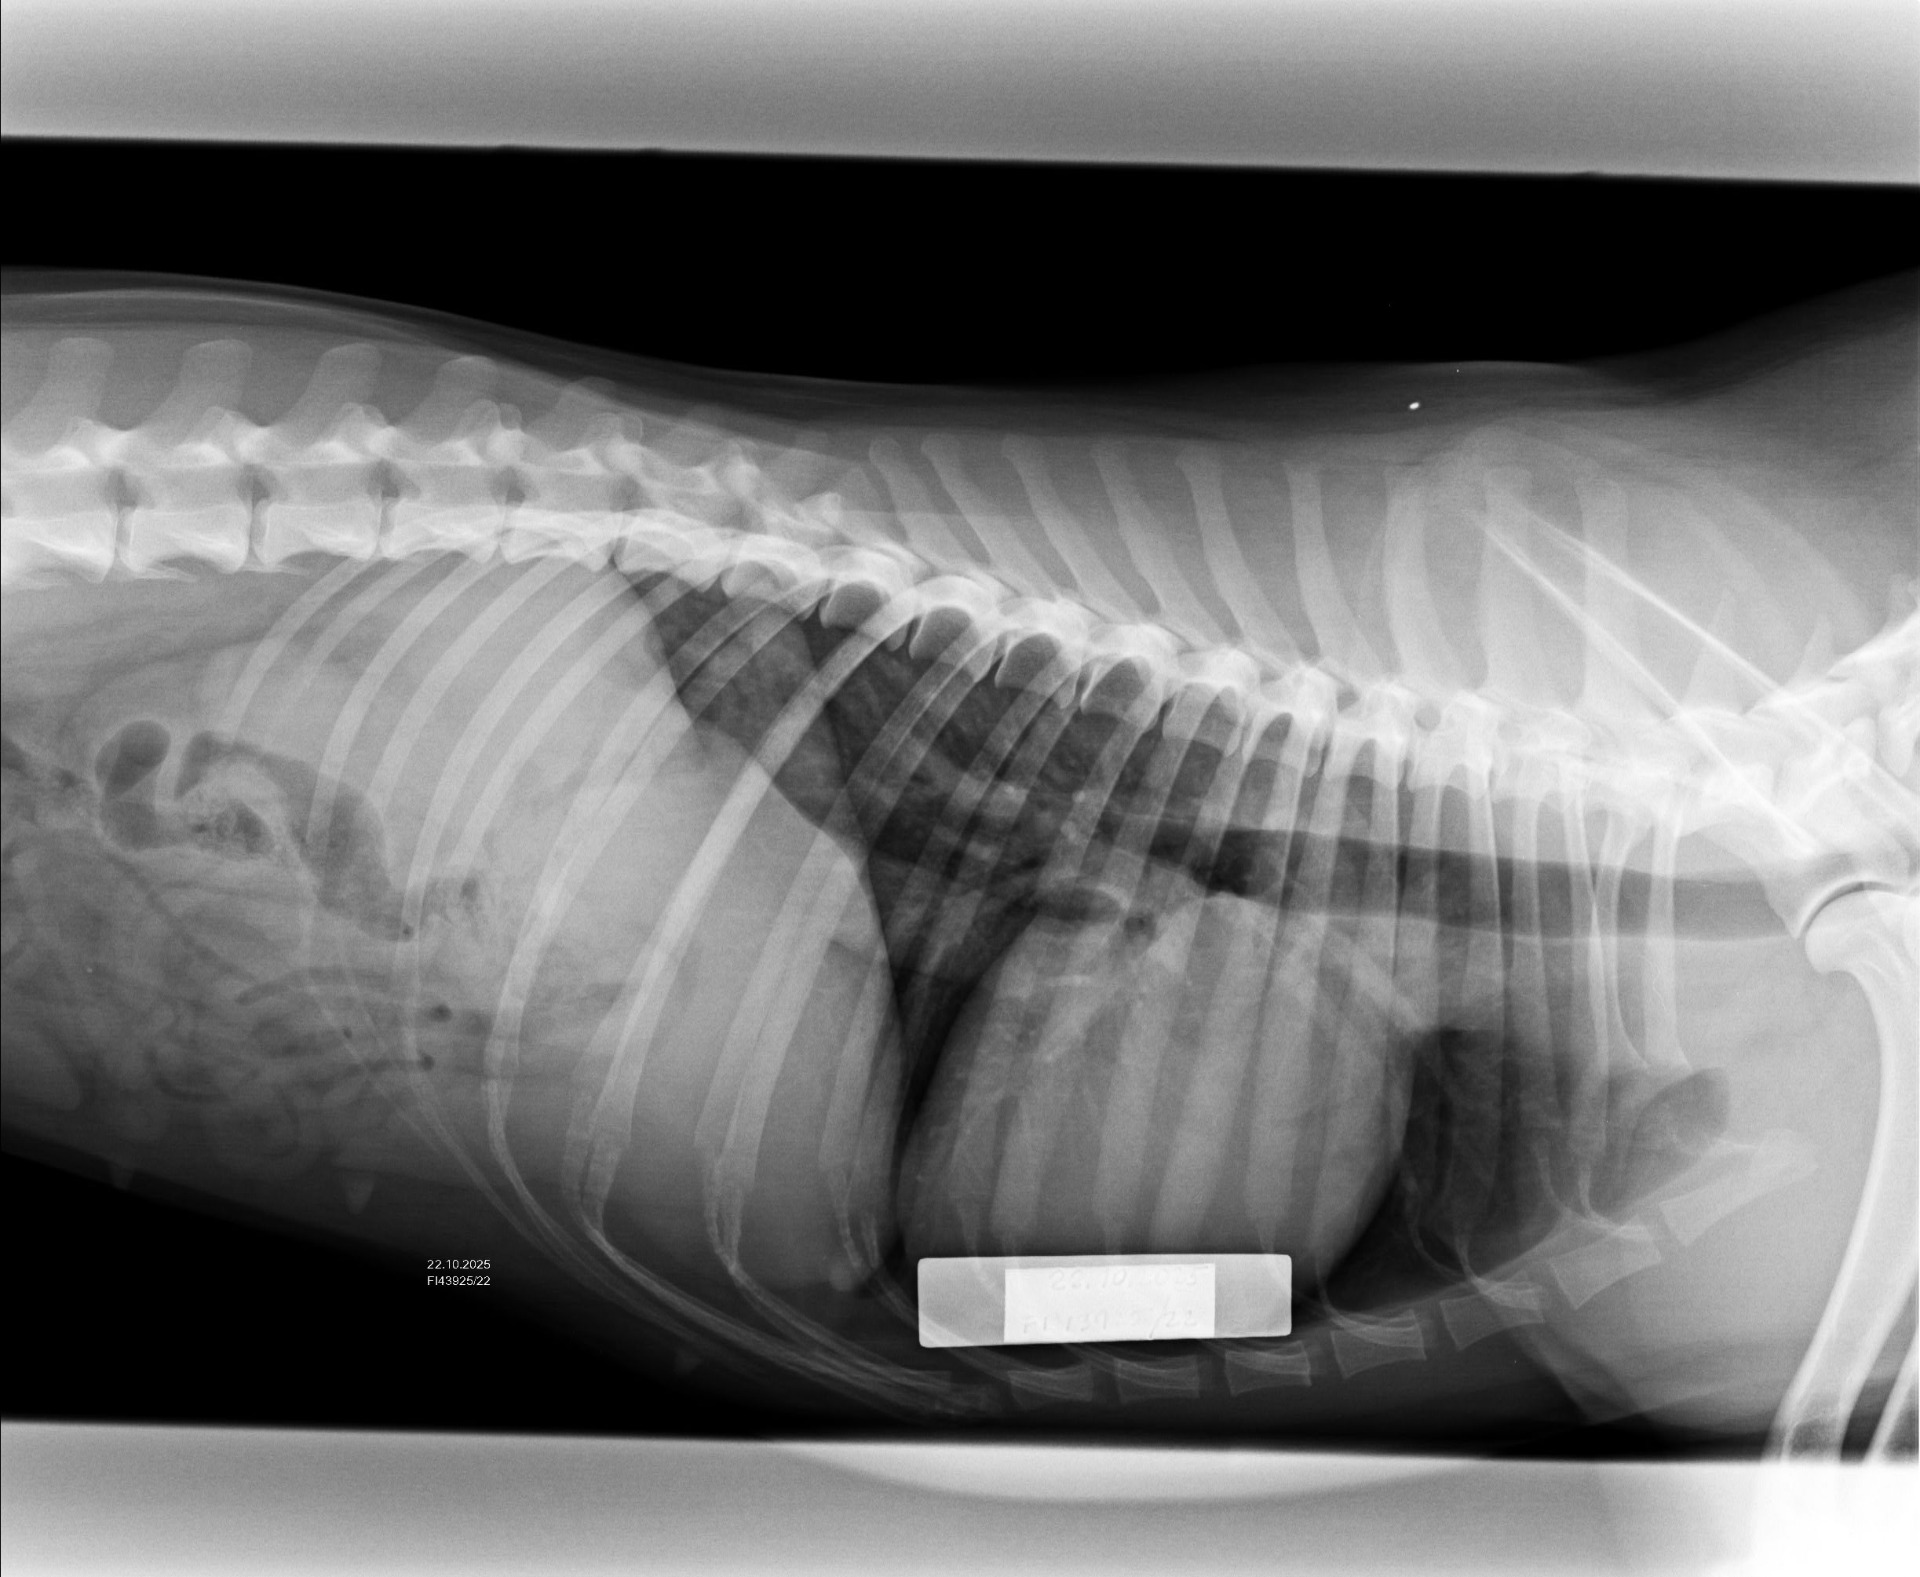

Keplerin viralliset luustokuvat

Kepler kävi kolmen sisaruksensa kanssa luustokuvilla tiistaina. Toki jo välikuvien perusteella tiesin melko hyvin mitä voi odottaa, joten niin paljoa ei jännittänyt, mutta toki silti vähän. Kuvat näytti kuitenkin oikein hyvältä, joten lausuntoja saattoi jäädä odottamaan levollisin mielin. Tänään tuli sitten viralliset tulokset, ja hienoltahan ne...